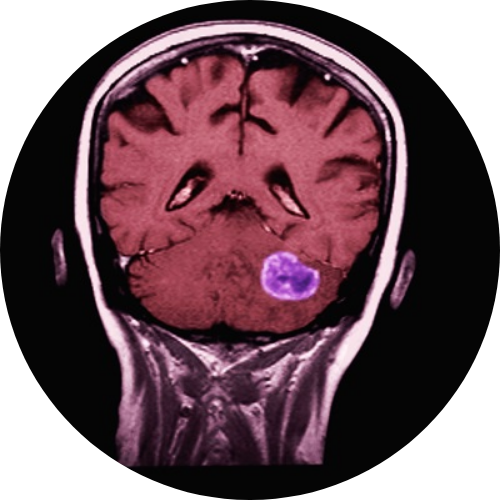

Base of skull surgery refers to procedures that access and remove tumors located at the bottom of the skull, behind the nose, around the sinuses, near the ear, or at the junction of the head and neck. These surgeries are performed using modern techniques that reduce trauma and improve recovery.

Skull base surgery begins with detailed imaging to understand the tumor’s position and the surrounding nerves and vessels. The surgical approach is planned to reach the area safely with minimum disruption. Depending on the location, surgeons may use endoscopic tools through the nose or small incisions around the head and neck.